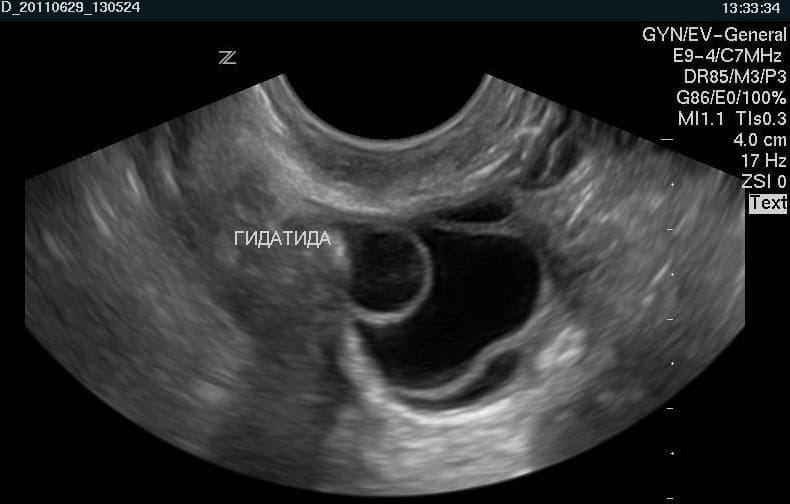

Гидатида Морганьи

Данные новообразования часто бывают круглой и овальной формы. Поверхность у них гладкая и достигает размера около 2 см.

Кисты висят на ножке, их еще называют привеском фаллопиевых труб. Чтобы проверить женщину на наличие гидатид, требуется ультразвуковое исследование. С его помощью диагностируются маточные трубы на предмет проходимости и новообразований. В случае, когда гидатида вырастает до трех сантиметров в диаметре, она может вызвать неприятные ощущения:

Гидатида яичника – это остаток эмбрионального мюллерова протока. Представляет собой полость размерами 2-8 мм с четкими ровными контурами. Гидатида соединена с яичником тонкой ножкой. Внутри образование содержит прозрачную серозную жидкость.